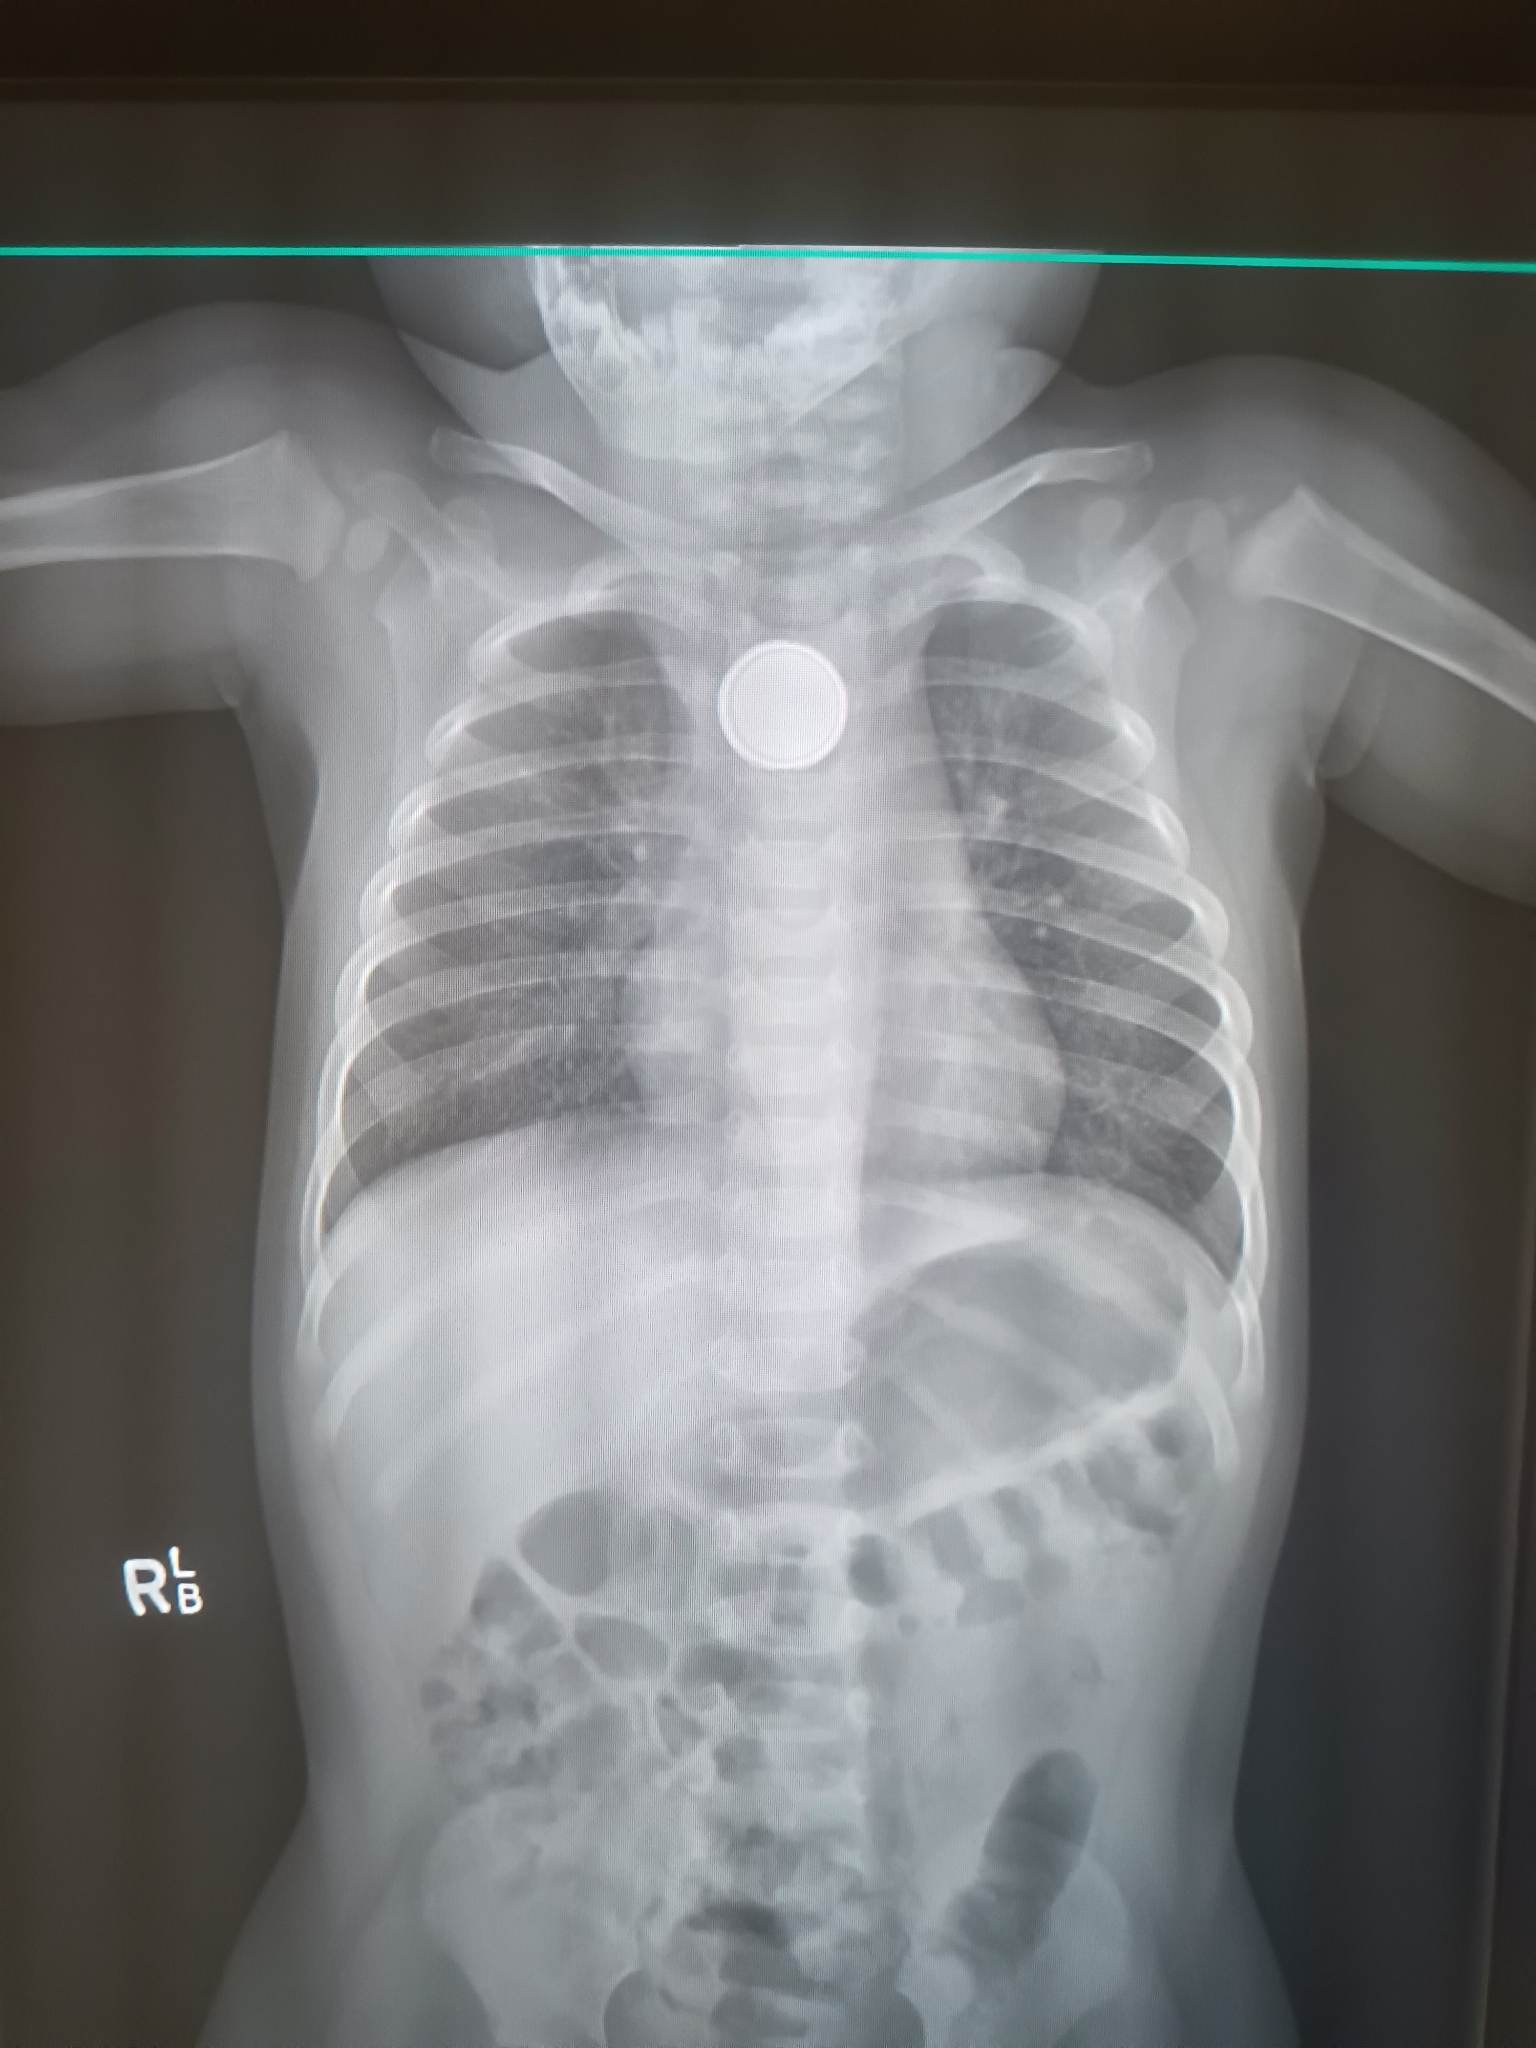

Amity x ray

One-year-old Amity did not receive an X-ray until her second trip to the emergency department.(Supplied: Daniel Buchanan )